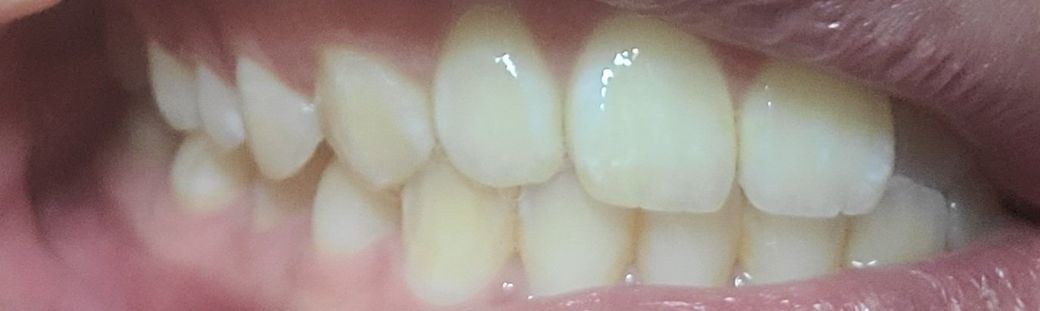

왼쪽1

왼쪽이 제1소구치쪽부터 교합이 아주 이상적인 교합은 아닙니다. 또한, 오른쪽 2번째 치아는 원래 위 치아가 아래치아를 덮어야하는데, 그렇지 않고 치아끼리 바로 닿습니다. 이 경우 치아에 무리가 갈 수 있습니다.

왼쪽 소구치와 대구치는 사진으로만 보기에는 정상적으로 교합하고 있는것으로 보입니다.